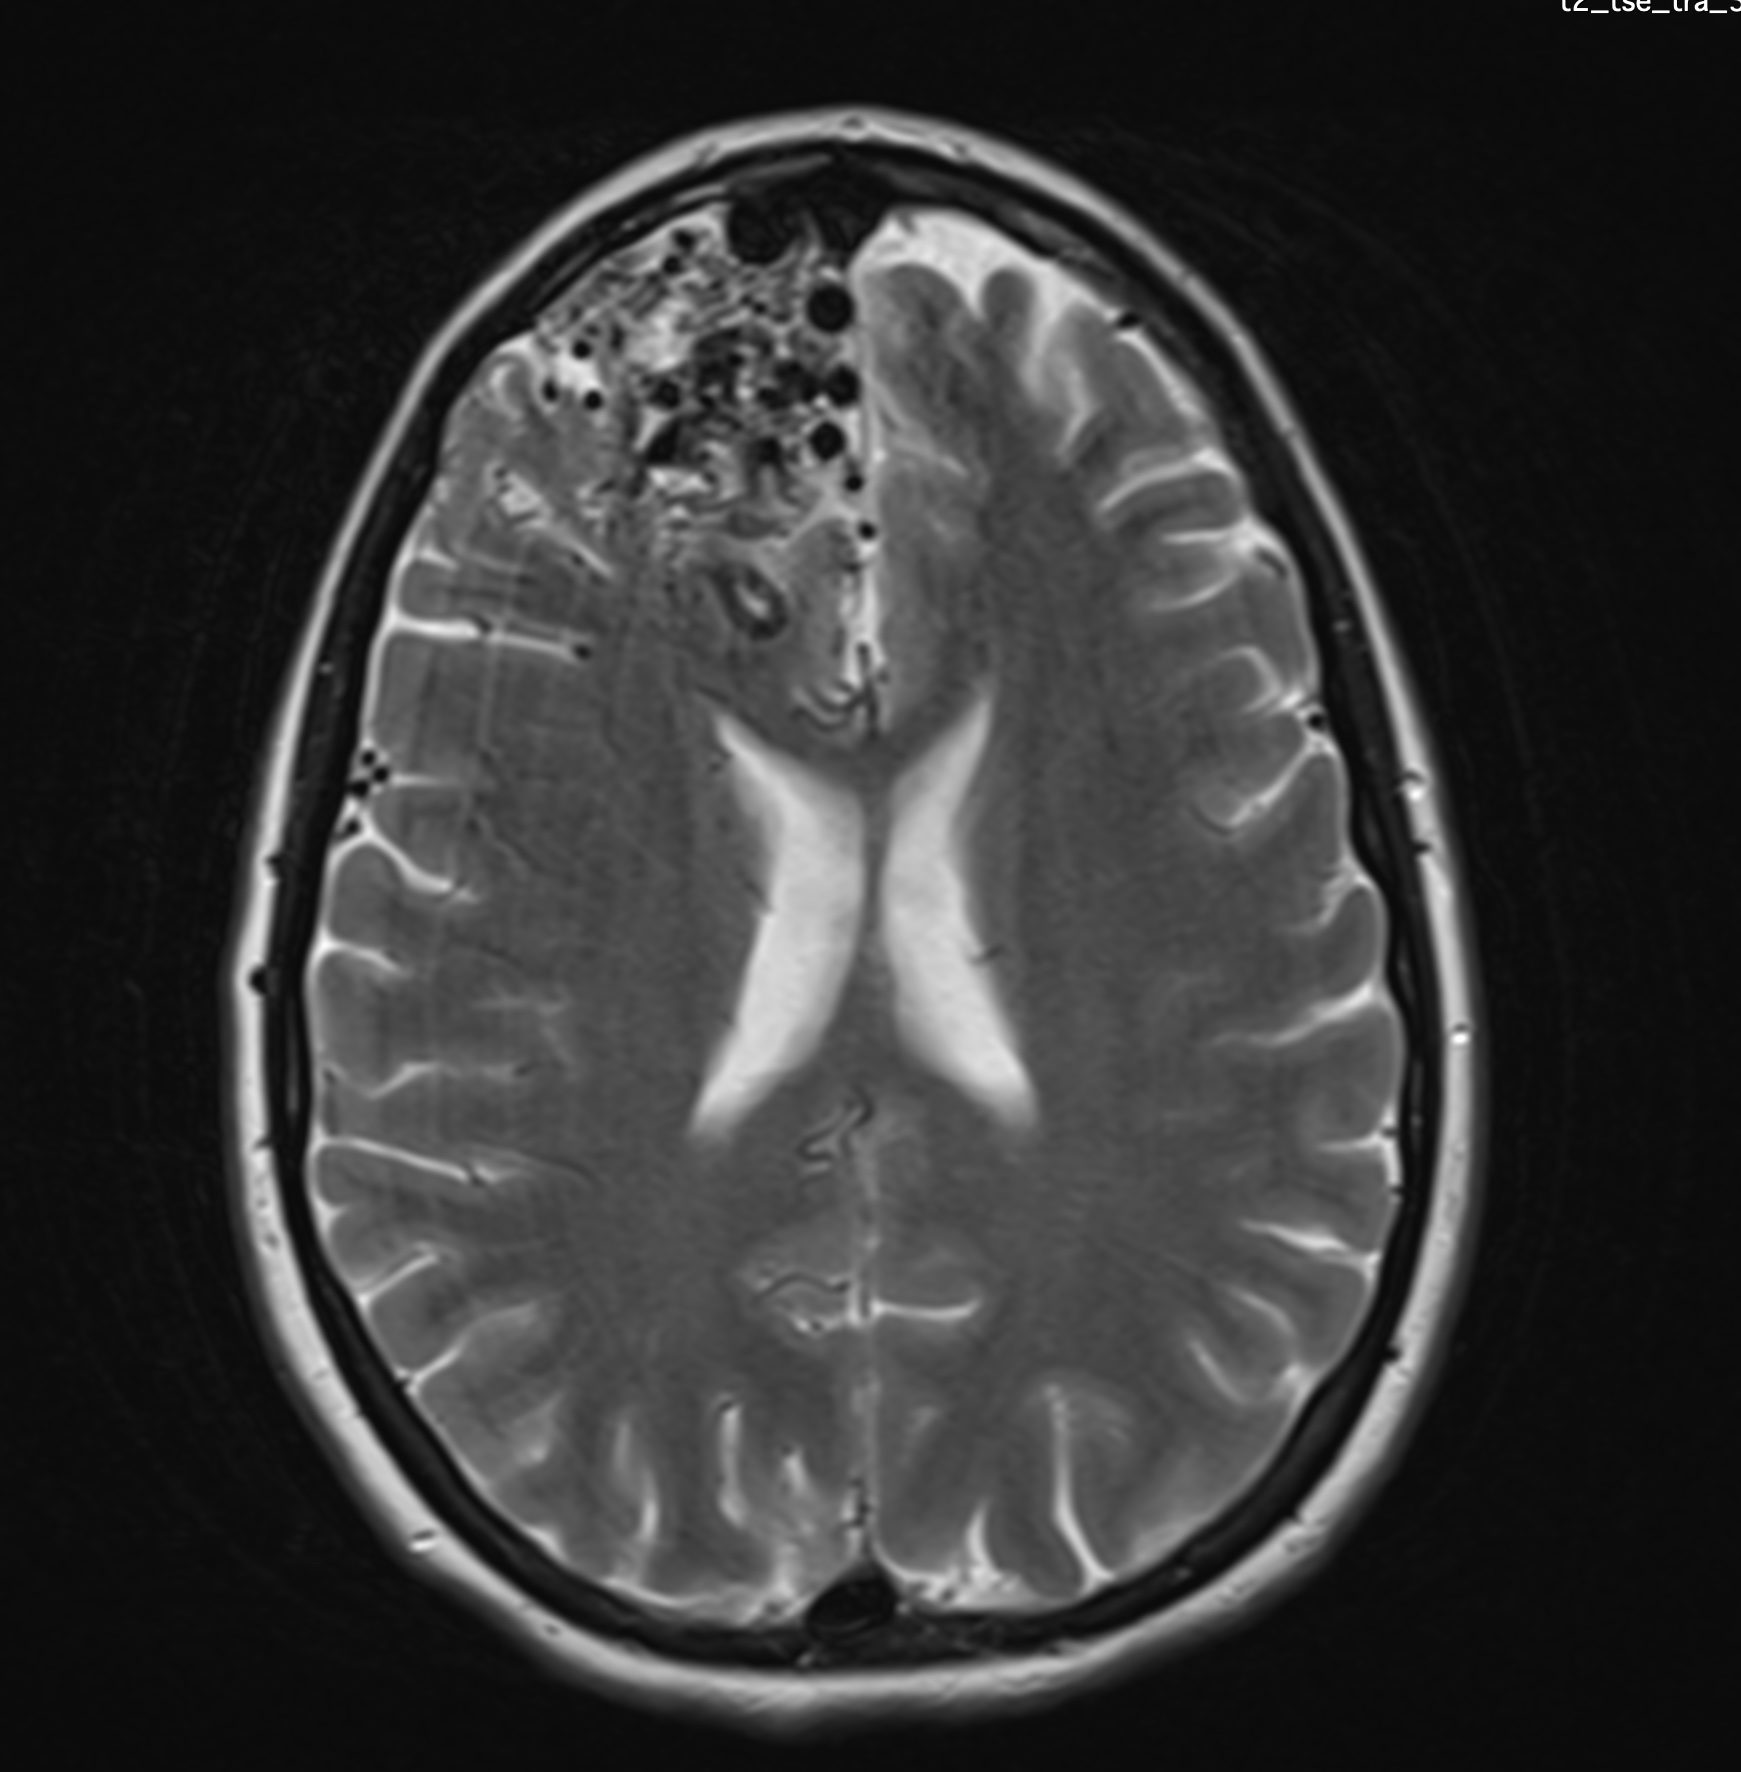

Multipli aneurismi su arterie cerebrali

L’aneurisma cerebrale è dovuto alla degenerazione della parete di un’arteria cerebrale. La sua formazione è un processo lento, favorito da fattori di rischio cardio-vascolari comuni (fumo, ipertensione arteriosa, colesterolo, diabete) ai quali si aggiungono alcuni fattori di rischio genetici. Un aneurisma cerebrale è molto raramente responsabile di un deficit neurologico se non è rotto. In rari casi di aneurismi di dimensione importante, l’aneurisma può provocare una compressione delle strutture neurologiche, come ad esempio un nervo cranico.

La scoperta occasionale di un aneurisma cerebrale è frequente e un parere specialistico neurochirurgico è assolutamente necessario. Secondo dei criteri precisi, si deve stabilire se l’aneurisma presenta un rischio elevato di rottura e, di conseguenza, di provocare un’emorragia cerebrale. In questo caso è possibile proporre un trattamento «preventivo» dell’aneurisma. I fattori di rischio che aumentano la probabilità di rottura dell’aneurisma sono le dimensioni della sacca sopra 7mm, la sua localizzazione su alcune arterie cerebrali, il fumo, la pressione arteriosa alta ed il numero di aneurismi presenti.

Esistono due trattamenti diversi per un aneurisma cerebrale: il clipping chirurgico ed il coiling endovascolare. Il Dr Robert e la dr.essa Bonasia hanno una grande esperienza nella presa decisionale e nei controlli degli aneurismi cerebrali. Sono specialisti per il clipping chirurgico degli aneurismi avendo realizzato più di 200 interventi di questo tipo. Si tratta di un trattamento che viene eseguito presso la Clinique La Source di Losanna.